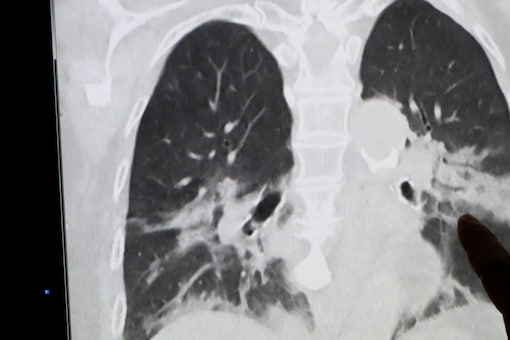

No entanto, eles não descobriram que era um caso de feto dentro de feto até que vários testes fossem realizados no recém-nascido. De acordo com o “Times of Israel“, o teste, que incluiu ultrassons e raios-X, mostrou que a menina tinha um feto parcialmente desenvolvido dentro do abdômen.

Estudo afirma que a condição ocorre em cerca de 1 em 500.000 nascimentos e é extremamente rara – Foto: ReproduçãoEstudo afirma que a condição ocorre em cerca de 1 em 500.000 nascimentos e é extremamente rara – Foto: Reprodução